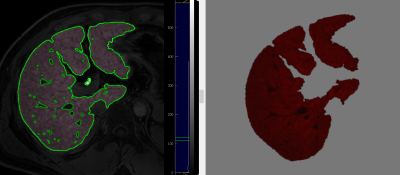

Demonstration of radiomics analysis on Gadoxetic acid-enhanced hepatobiliary phase (HBP) axial MR image at hepatic portal level in a 54-year-old man with hepatitis B–related liver cirrhosis.

Train and test ROCs for liver function.